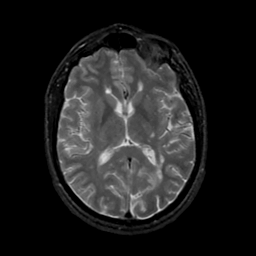

MR Study #17, July 7, 1991 -- Slice #27